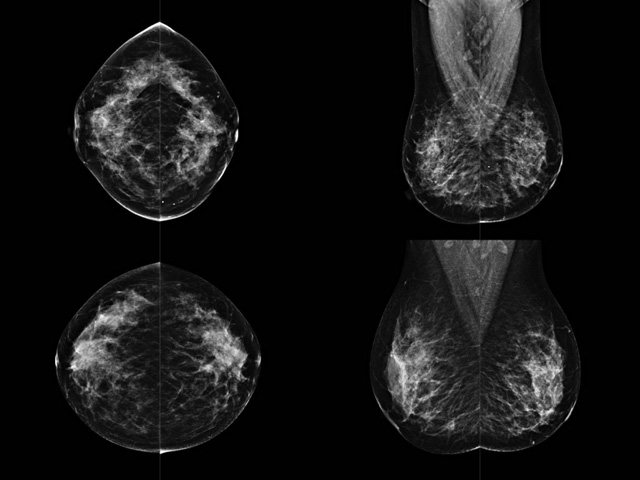

乳房檢查時候要注意一些細節,需要更深入的了解這樣才能使檢查更準確。乳腺DR是乳腺癌的篩查診斷工具設備。是乳房方面檢查的重要影像方法。它可以臨床檢查出早期的乳腺癌??梢耘袛嗔夹詯盒?。因為它可以檢查出早期的病變。對良性惡性檢查的準確率達到90%以上。發病高峰年齡為45歲到54歲。50歲檢查出來乳腺癌病患,可以讓死亡率下降3成。所以30-40歲女性每年做一次乳腺DR檢查。40歲以上就一年兩次。如果家族史有乳腺癌的30歲以下也需要做檢查。清晰顯示乳腺各層組織嚴重的乳腺增生,乳腺炎,乳腺外傷也建議1年檢查一次。極大提高了早期乳腺癌的敏感度和診斷率。

大角度、高質量的乳腺檢查,可以讓女性帶來身體健康安全。為醫生提供了高清影像數據。乳腺檢查時候各個部位影像顯示出來。白色乳腺導管跟纖維結締組織。模糊的是脂肪。病變一般是不透明的白色。有需要放大來檢查。乳腺DR沒有重疊偽影。輻射劑量更少。因為乳腺癌發病每年都有所提高,對女性都造成了嚴重的身體健康危害。早做檢查早治療是不可忽視的舉措??梢源蟠蟮慕档?/span>死亡率。保證身體健康。一般檢查避開經期,來完7天左右是最佳的檢查時間。絕經的女性就沒有要求。孕婦不參加乳腺DR檢查, 6個月內準備妊娠的婦女也不宜行此檢查。